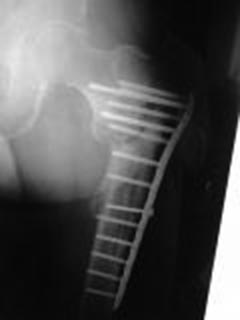

Мужчина 63 года, травма в феврале 2013 г. - перелом в/3 левой бедренной кости. В ЦРБ остеосинтез пластиной LCP. 17.06.2014 г. пластина удалена, стал отмечать боли, патологическую подвижность в бедре, укорочение левой нижней конечности на 4 см. 04.02.2015 г. в одном из учреждении г. Москвы произведена резекция ложного сустава, остеосинтез пластиной с пластикой Коллапаном. На сегодняшний момент беспокоят боли и патологическая подвижность в области верхней трети левого бедра, укорочение конечности на 4 см, передвигается при помощи костылей с нагрузкой на оперированную конечность. Рентгенограммы от 21.04.2015 г. и 16.08.2015 г.В отделении планируется: удаление пластины, остеотомия, восстановление ШДУ, фиксация стержнем. Вопрос: возможно ли выполнить операцию одномоментно или необходимо аппаратное удлинение бедра?

Да уж оба раза поработали "спецы". Снимок не очень что-то. По тому что рассмотреть удалось- вроде можно одномоментно. Стержень надо попрочнее, ШДУ чуть в вальгус. Удостовериться в отсутствии инфекции.

План вполне рациональный, но лучше бы увидеть схему того, что предполагается сделать. Где остеотомию, как будут располагаться отломки.

Чтобы ответить насчет длины - надо иметь что-то для измерений. Или снимок обеих нижникх конечеостей на одной пленке, либо можно уложить пациента на спину, выровнять таз, сделать снимки обоих проксимальных бедер на одной пленке, и обоих коленок на другой, не меняя положение пациента. Тогда будет хорошо видна разница длин, и будет понятнее, что получится от одной угловой коррекции.